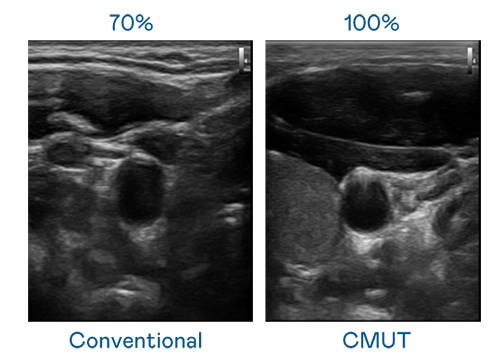

CMUT 技術是一種用電容式微機電元件來產生超音波訊號的技術。與傳統 PZT 壓電式技術相比,CMUT 頻寬增加 30%,更寬頻的超音波訊號讓影像解析度大幅提升,是實現高影像品質醫療超音波掃描、促進精準醫療發展的關鍵技術。

超音波影像的解析度高低,首先取決於探頭能發出的訊號頻寬。金沙城 CMUT 可提供高清晰的超音波訊號,提供高頻寬、高靈敏度、影像紋理細節更高的超音波影像,協助醫護人員縮短影像判讀時間及利用精準的醫療影像進行診斷。